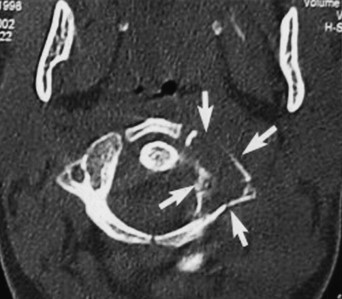

• C2椎弓に主座を置く溶骨性かつ膨張性の腫瘤性病変。

• CTにて辺縁に硬化縁を伴う。歯突起に病的骨折あり。

• CT

• 左:CT(骨条件)、右:造影CT